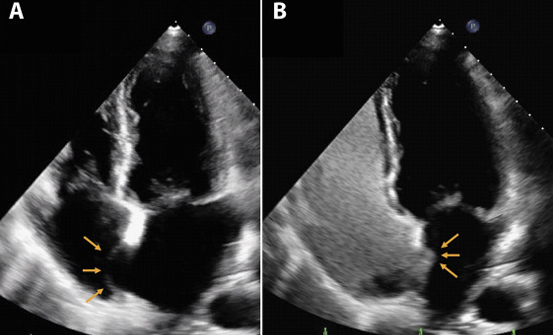

• A- Without Bubble Contrast

• B- With bubble contrast, showing no hole in the upper heart chambers in an anuerysmal intra-atrial septum